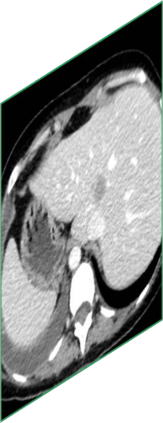

Due to the constraints of the imaging device and high cost in operation time, computer tomography (CT) scans are usually acquired with low intra-slice resolution. Improving the intra-slice resolution is beneficial to the disease diagnosis for both human experts and computer-aided systems. To this end, this paper builds a novel medical slice synthesis to increase the between-slice resolution. Considering that the ground-truth intermediate medical slices are always absent in clinical practice, we introduce the incremental cross-view mutual distillation strategy to accomplish this task in the self-supervised learning manner. Specifically, we model this problem from three different views: slice-wise interpolation from axial view and pixel-wise interpolation from coronal and sagittal views. Under this circumstance, the models learned from different views can distill valuable knowledge to guide the learning processes of each other. We can repeat this process to make the models synthesize intermediate slice data with increasing inter-slice resolution. To demonstrate the effectiveness of the proposed approach, we conduct comprehensive experiments on a large-scale CT dataset. Quantitative and qualitative comparison results show that our method outperforms state-of-the-art algorithms by clear margins.